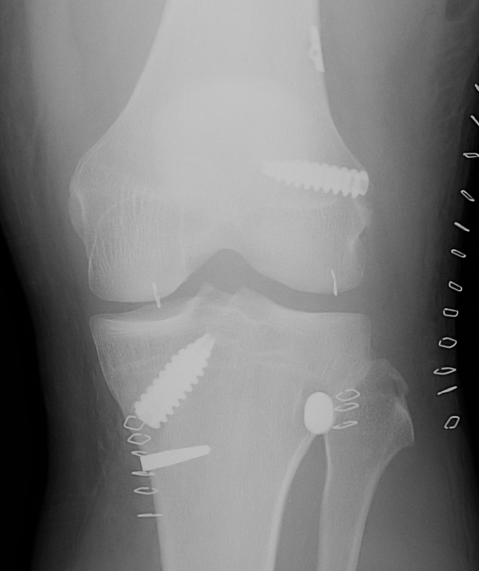

CT demonstrating ACL and PCL tunnels

Xray following PCL reconstruction, LCL and politeus reconstruction. CT demonsrating popliteus and LCL tunnels